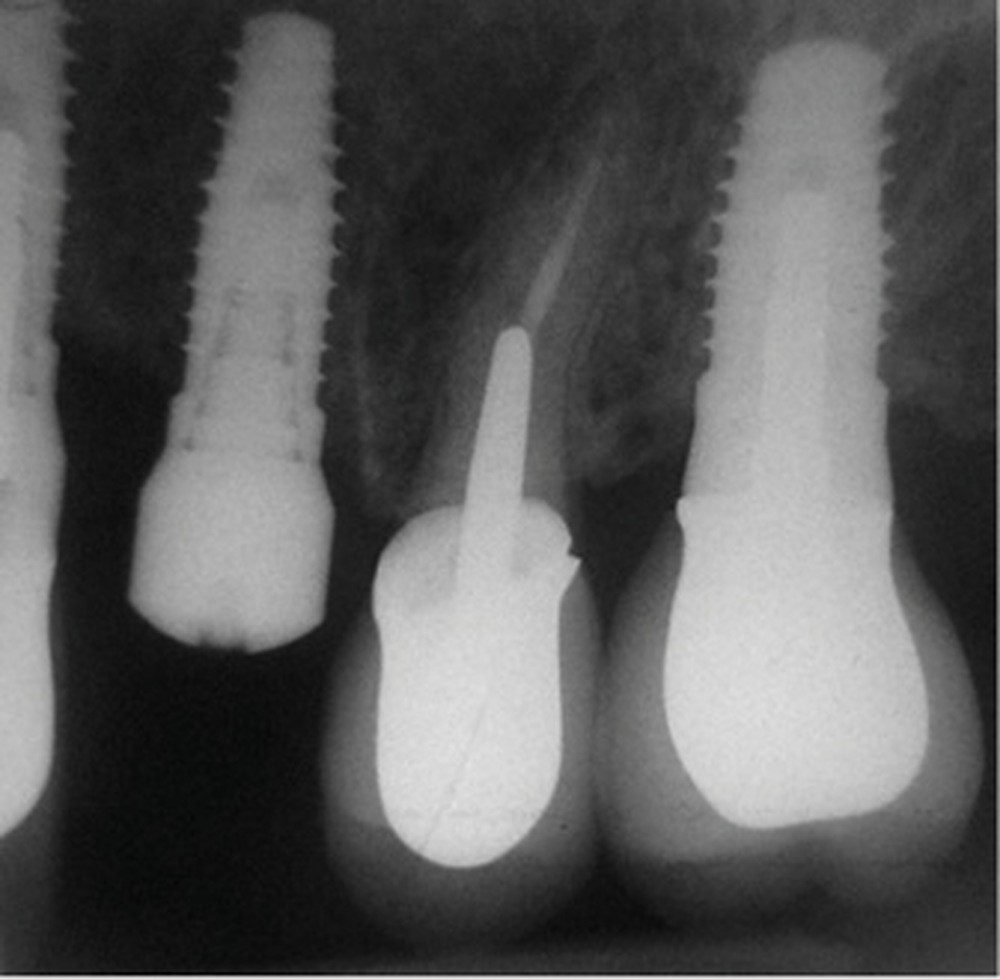

La radiographie péri-apicale au long cône confirme, sur la 25, un élargissement desmodontal, notamment en distal, des niveaux osseux mésio-distaux réduits par rapport aux clichés de contrôle précédents (les radiographies sont réalisées avec une technique parallèle avec des angulateurs de Rinn non personnalisés), un apex radiculaire normal et des niveaux osseux stables sur les implants adjacents (fig. 5). Le cisaillement systématique du fil dentaire lors de son passage confirme des points de contact très étroits entre 24, 25 et 26.